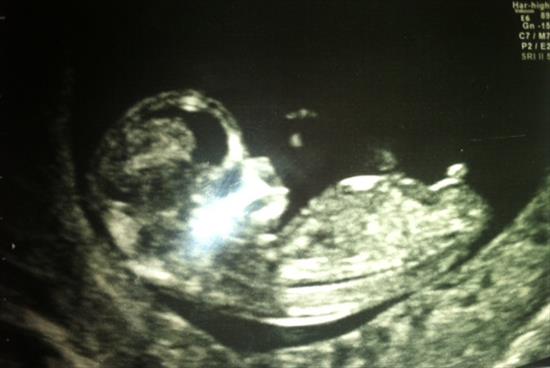

We had our 12 weeks scan and we were wondering if any of you could guess the gender?